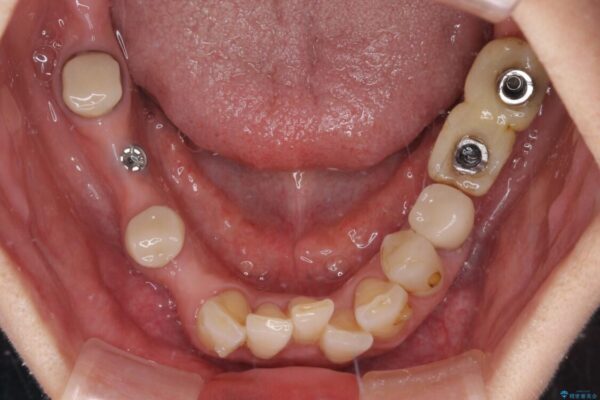

治療前

• 放置したインプラントとインビザライン 全顎リカバリー治療 治療前画像

治療途中